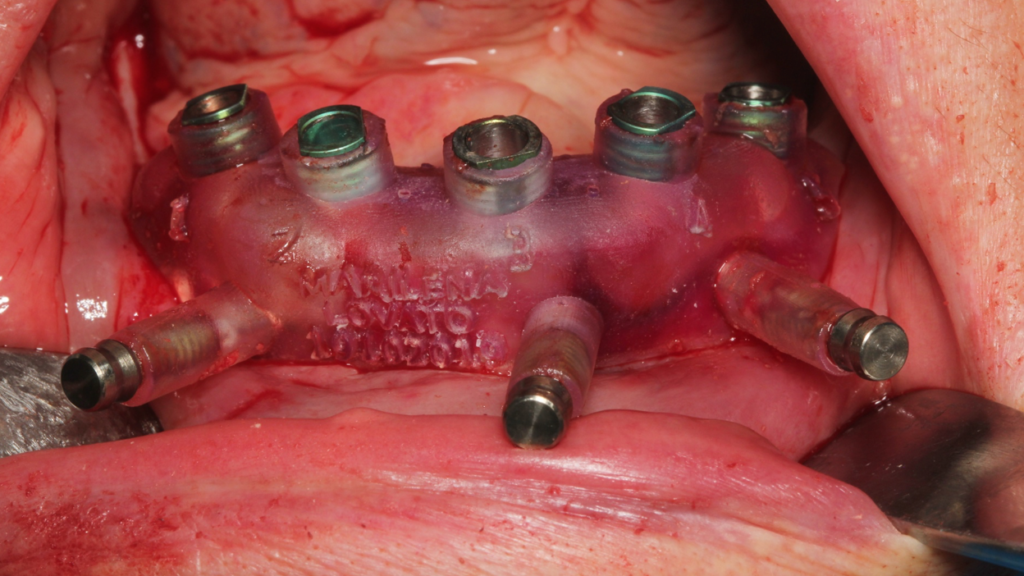

Através do programa Blue Sky (em parceria com a empresa Odontoplanning), foi feito planejamento guiado com 2 guias. O primeiro guia de recorte ósseo, tem como objetivo o recorte e aplainamento ósseo, deixando uma altura óssea mais uniforme entre a região posterior e anterior da mandíbula.

Através da imagem do osso recortado é planejada a guia de perfuração que vai se encaixar de uma maneira perfeita no osso recortado.

Lembrando que essas guias serão apoiadas exclusivamente no osso, sem envolvimento de mucosa, portanto há que se fazer incisão e descolamento mucoperiostal suficiente para o encaixe da guia.